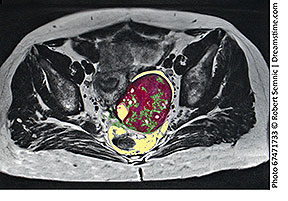

ULTRASOUND DIAGNOSTICS OF ENDOMETRIOMA - By: Dr. Robert L. Bard

Endometriosis starts in the endometrium with abnormal cellular proliferation. Through the use of 3D Ultrasound, this disorder can be measured through the monitoring of the widening or the increased tissue in the endometrium. Another form of quantitative measure is by the study of blood flow in the endometrium. Its ability to spread can be recognized by the number of vessels in the active tissue. The big problem with staging endometriosis (or endometriomas) are the cysts that follow it. Because of its capacity to spread in most areas of the body, a strategic protocol for clinical management is to conduct IMAGE GUIDED treatments, whereby use of real-time scanning of or during therapeutic process helps navigate the focus the treatment area. Imaging solutions include CT (which has radiation), MRI, or the 3D Doppler ultrasound. (See full feature)